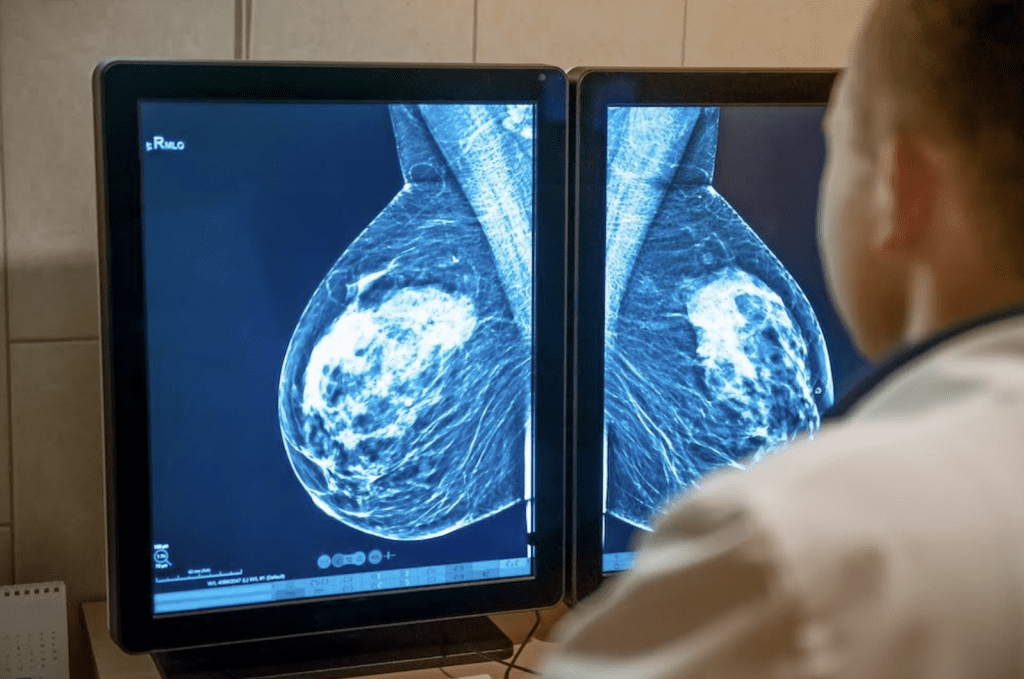

En México, el cáncer de mama sigue siendo una de las principales causas de muerte en mujeres. Con una tasa de 19.8 defunciones por cada 100 mil mujeres y un promedio de 22 fallecimientos diarios, el panorama exige algo más que campañas de concientización: requiere innovación clínica con impacto real.

En este contexto, ALIA Health, spin-off de TecSalud del Tecnológico de Monterrey, y ÜMA Tech IA, Partner de Servicios de Google Cloud para el sector salud en Latinoamérica, anunciaron el desarrollo de ALIA Health Risk Platform, una plataforma basada en inteligencia artificial que permite anticipar el riesgo de desarrollar cáncer de mama en un horizonte de cinco años, a partir de mamografías convencionales.

El corazón de la plataforma es Mammorisk+, un modelo predictivo entrenado con datos reales de práctica clínica. A diferencia de herramientas que detectan lesiones ya sospechosas, este modelo estima la probabilidad futura de desarrollar cáncer de mama en mujeres cuyas mamografías no muestran hallazgos preocupantes.

El objetivo es claro: actuar antes del diagnóstico, en la etapa donde se definen estrategias de prevención, seguimiento y personalización del tamizaje.

En un país donde solo el 27% de las mujeres en edad de riesgo tuvo acceso a una mastografía el último año y donde el 64% de los casos se detectan en etapas II o III —cuando los tratamientos son más costosos y la supervivencia disminuye—, esta herramienta podría representar un punto de inflexión.